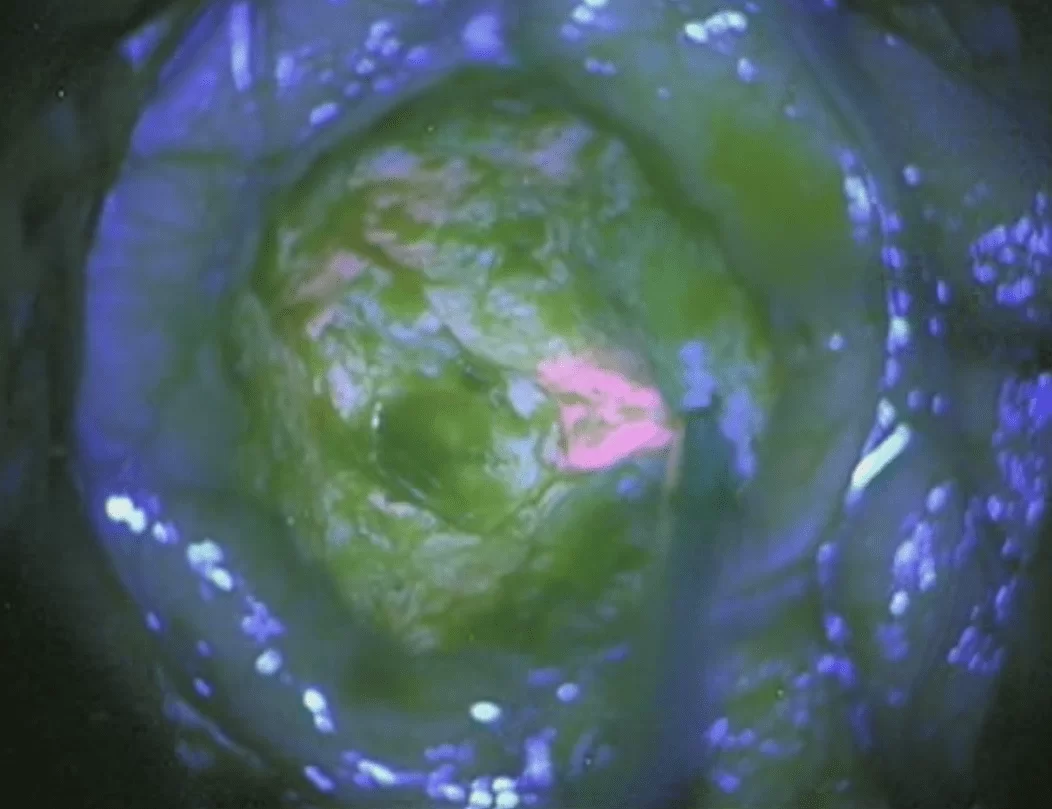

Ο Παντελής Σταυρινού είναι εξειδικευμένος στην αντιμετώπιση γλοιωμάτων. Ο συνδυασμός δεκαετούς εμπειρίας στην Πανεπιστημιακή Κλινική της Κολωνίας, μια από τις πρώτες νευροχειρουργικές κλινικές οι οποίες έλαβαν πιστοποίηση αριστείας στην αντιμετώπιση των όγκων εγκεφάλου και του υπερσύγχρονου εξοπλισμού που προσφέρει το Metropolitan Hospital (3D-3K εξωσκόπιο ORBEYE, χρήση ανοσοφθορισμού 5-ALA, διεγχειρητική νευροπλοήγηση και υπέρηχος, ηλεκτροφυσιολογικός έλεγχος και δυνατότητα αφαίρεσης όγκων με τον ασθενή σε εκγρήγορση (ξύπνιο) εγγυώνται εξατομικευμένη και αποτελεσματική φροντίδα ακόμη και στα πιο απαιτητικά περιστατικά.

Χειρουργική αφαίρεση – Ο στόχος της χειρουργικής επέμβασης είναι η απομάκρυνση όσο το δυνατόν περισσότερου όγκου χωρίς βλάβη στον υγιή εγκέφαλο. Τα δεδομένα της σύγχρονης βιβλιογραφίας δείχνουν ότι η αφαίρεση της βλάβης, ακόμη και αν είναι υφολική (δηλ. αν δεν αφαιρεθεί ολόκληρος ο όγκος), έχει πλεονεκτήματα για την πρόγνωση. Όμως δεν είναι ακόμη σαφές πόσος όγκος πρέπει να αφαιρεθεί προκειμένω ο ασθενής να έχει σημαντικό όφελος από την επέμβαση.

Τα χαμηλόβαθμα αστροκυττώματα αναπτύσσονται σε υγιή εγκέφαλο και συχνά δεν υπάρχει σαφές όριο μεταξύ του όγκου και του φυσιολογικού εγκεφάλου. Ως εκ τούτου, ενδέχεται το χειρουργείο να μην αφαιρέσει όλα τα κύτταρα του όγκου, μερικά απο τα οποία μπορεί να βρίσκονται ανάμεσα σε απολύτως υγιή εγκεφαλικά κύτταρα. Έτσι, τα κύτταρα του γλοιώματος που δεν αφαιρέθηκαν συνεχίζουν να αναπτύσσονται, προκαλώντας υποτροπή του όγκου. Έτσι, η χειρουργική επέμβαση, ακόμη και όταν είναι εκτεταμένη, πολλές φορές δεν επιτυγχάνει τη θεραπεία ενηλίκων με χαμηλόβαθμο αστροκύττωμα.